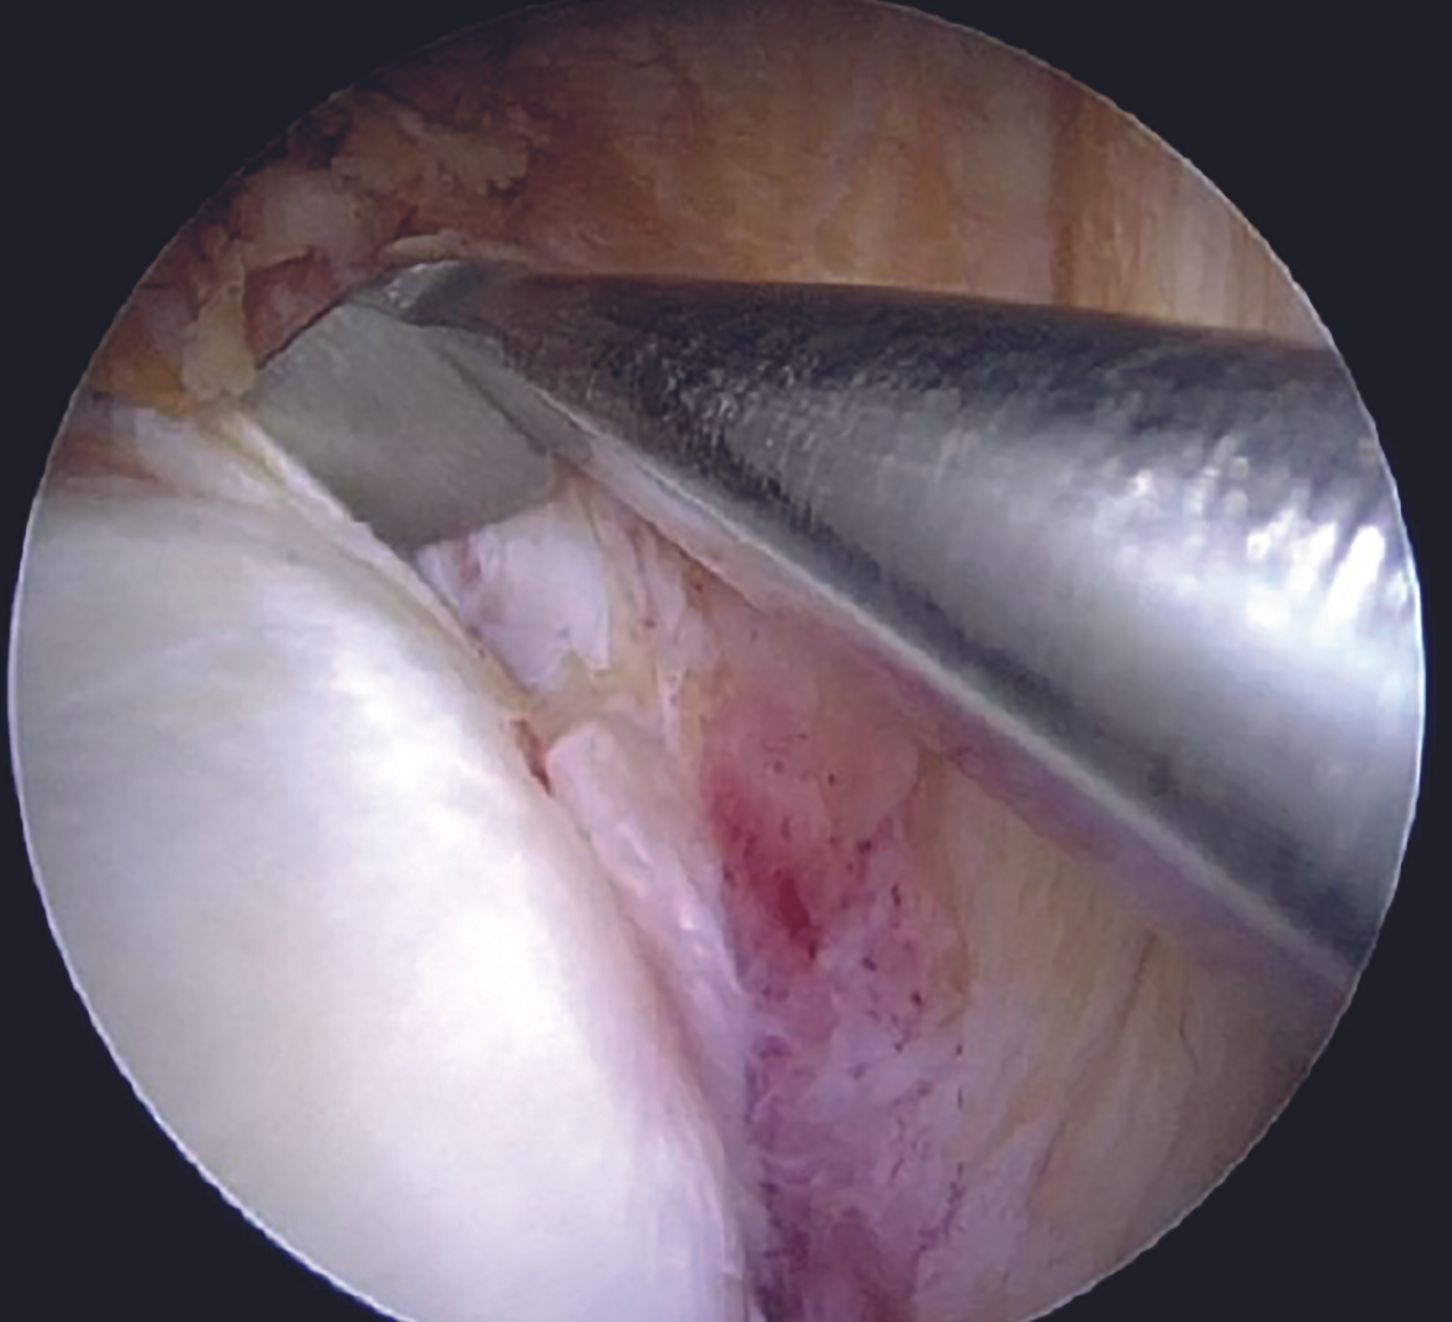

Capsulolabral tissue is mobilized using 15 and 30 degree arthroscopic tissue elevators sequentially (Figure 6).

Adequate mobilization of the labral tissue from glenoid neck remains a crucial step for an effective Bankart repair. Adequacy of the labral mobilization is indicated by floating of the labral tissue at the level of articular surface of the glenoid. Care should be taken while liberating the labral tissue at 6 O'clock position in order to prevent an injury to the axillary nerve. Frayed tissue at the edge of the glenoid is cleared using a motorized 3.5mm arthroscopic shaver (Figure 7). Anterior glenoid bony surface is freshened with the help of a rasp in order to promote healing (Figure 8).